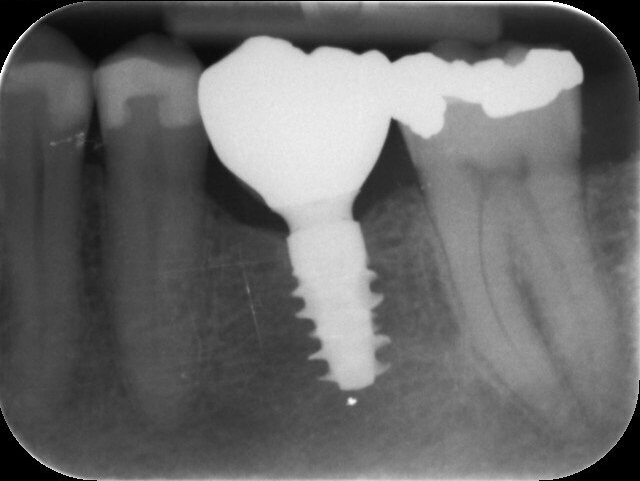

Fig. 6: Radiograph confirming the seating of a healing abutment of 6.5 mm in diameter and 1.5 mm in gingival height.

Fig. 12: Radiograph confirming the correct seating of the temporary crown—no gap visible.

Fig. 19: Radiograph confirming the correct seating of the final crown—no gap visible.

Fig. 22: One-year follow-up radiograph.